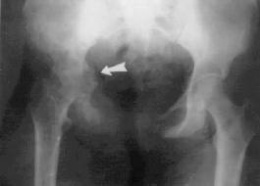

Durante un examen físico, el médico buscará pérdida del movimiento de la cadera y cojera característica. Una radiografía de la cadera o una radiografía de la pelvis pueden mostrar signos de enfermedad de Legg-Calve-Perthes. Se puede necesitar una resonancia magnética.